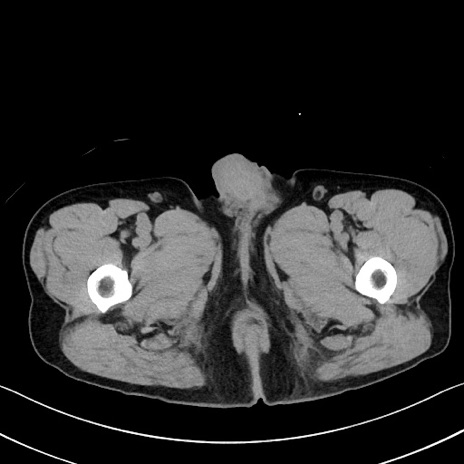

症例35(横断像)

【症例】70歳代 男性

【主訴】腹部膨満、嘔吐

【現病歴】昨日より腹部膨満感出現。本日増悪し、仙痛出現。嘔吐あり、受診。

【既往歴】糖尿病、胆摘後

【身体所見】BP 149/80mmHg、HR 74/min、BT 35.9℃、腹部:膨満、軟、圧痛なし。腸雑音減弱あり。上腹部正中切開瘢痕あり。

【データ】WBC 13500、CRP 1.72